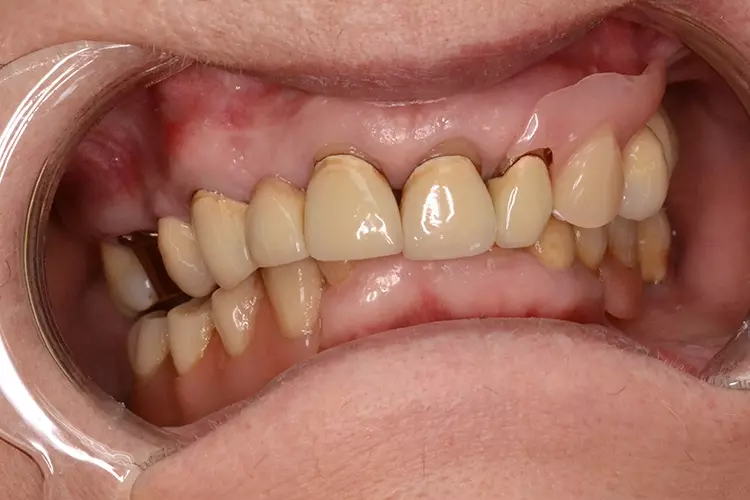

Neugestaltung der Front bei starken Zahnfehlstellungen

Bei dem heute 49-jährigen Patienten wurde seit Kindertagen versäumt, die Ober- und Unterkieferzahnbögen kieferorthopädisch auszurichten. Der Patient leidet seitdem stark unter seinen Zahnfehlstellungen.

Die Fraktur des stark elongierten Zahnes 21 war für den Patienten der Ausgangspunkt, sowohl die Front des Ober- als auch des Unterkiefers prothetisch überarbeiten zu lassen. Dabei wurde der frakturierte Zahn 21 durch ein navigiert eingesetztes Sofortimplantat ersetzt, während die verschachtelt stehenden Zähne 12 und 42 durch eine Brückenversorgung korrigiert wurden (Abb. 4a-j).